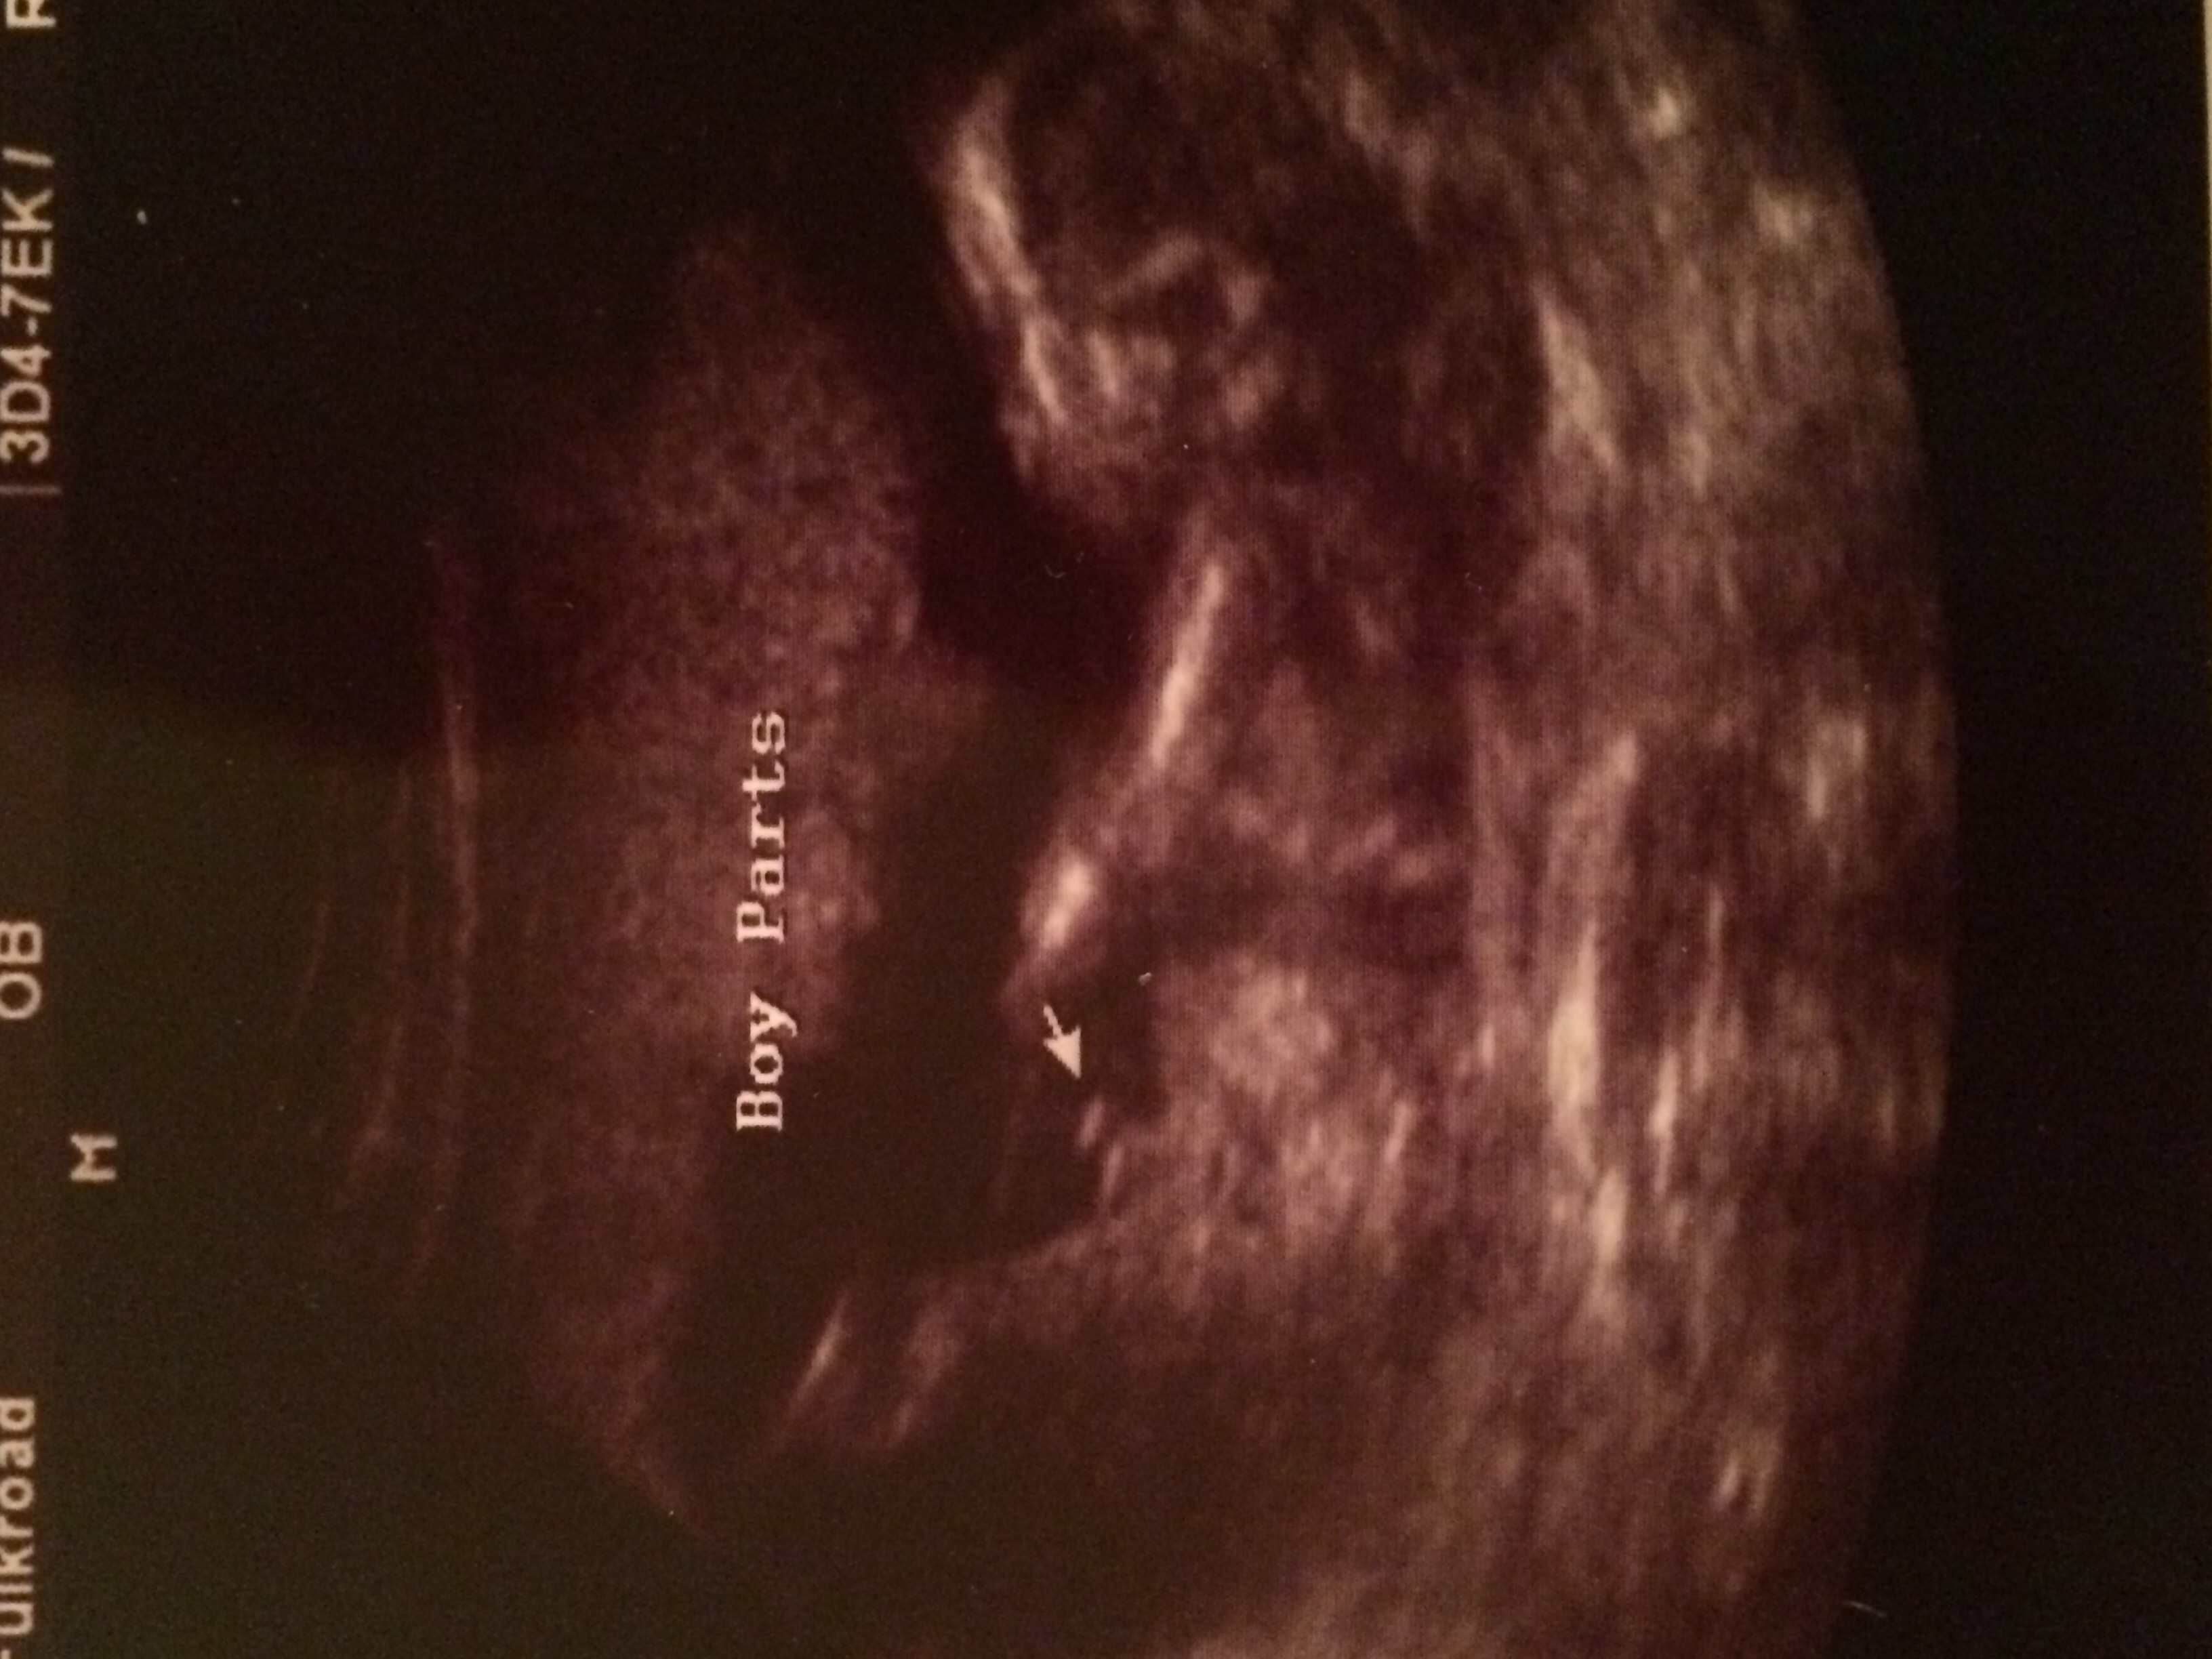

Our first baby is going to be a BOY!!!! He was quite proud & showing off. Momma & Daddy are THRILLED!! :) :x